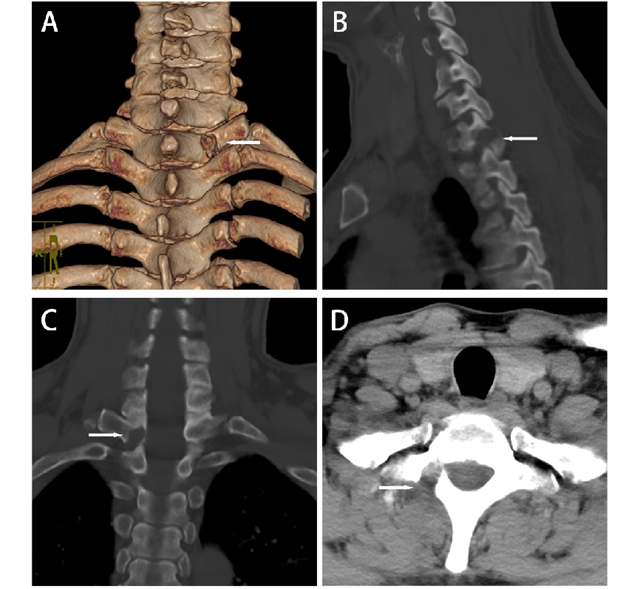

患者术后复查CT三维重建图像